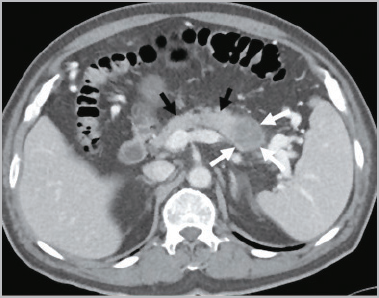

췌장암은 조기 발견이 가장 어려운 암 중 하나로 알려져 있습니다. 위치상 주변에 중요한 혈관이 얽혀있고, 암 발생 시 전이 위험도 매우 높은 것으로 알려져 있어 다른 암에 비해 진단이 쉽지 않고 치료도 쉽지 않아 실제 진단을 받았을 때는 이미 수술적 치료가 늦은 경우가 많은 것으로 알려져 있습니다.

황달은 췌장 머리에 생긴 종양이 소장으로 이어지는 총담관 부분을 막아 담즙의 흐름을 막고 혈중 빌리루빈 수치를 상승시킬 때 발생하는데, 췌장 머리에 생긴 암의 약 80%에서 발생합니다. 몸통이나 꼬리에 생긴 종양의 5~6%만이 황달을 유발하며, 황달이 발생할 때는 이미 암세포가 췌장 전체에 퍼져 간이나 림프절로 전이된 경우가 대부분입니다. 혈중 빌리루빈 수치가 증가하여 황달이 발생하면 피부와 눈 흰자위가 노랗게 변하고 소변 색이 갈색으로 변하며 대변 색이 회백색으로 변하고 피부가 가렵습니다.

췌장암의 가장 효과적인 치료법은 수술적 절제이지만, 이는 췌장암 환자의 약 20~25%에서만 가능합니다. 실제로 황달이 초기 증상인 췌장 머리에 종양이 있는 환자에 국한되는 경우가 대부분이며, 수술이 불가능한 췌장암 환자의 평균 생존기간은 약 6개월로 이들 환자의 치료 목표는 생존 기간 동안 증상을 완화하고 삶의 질을 개선하는 것입니다.